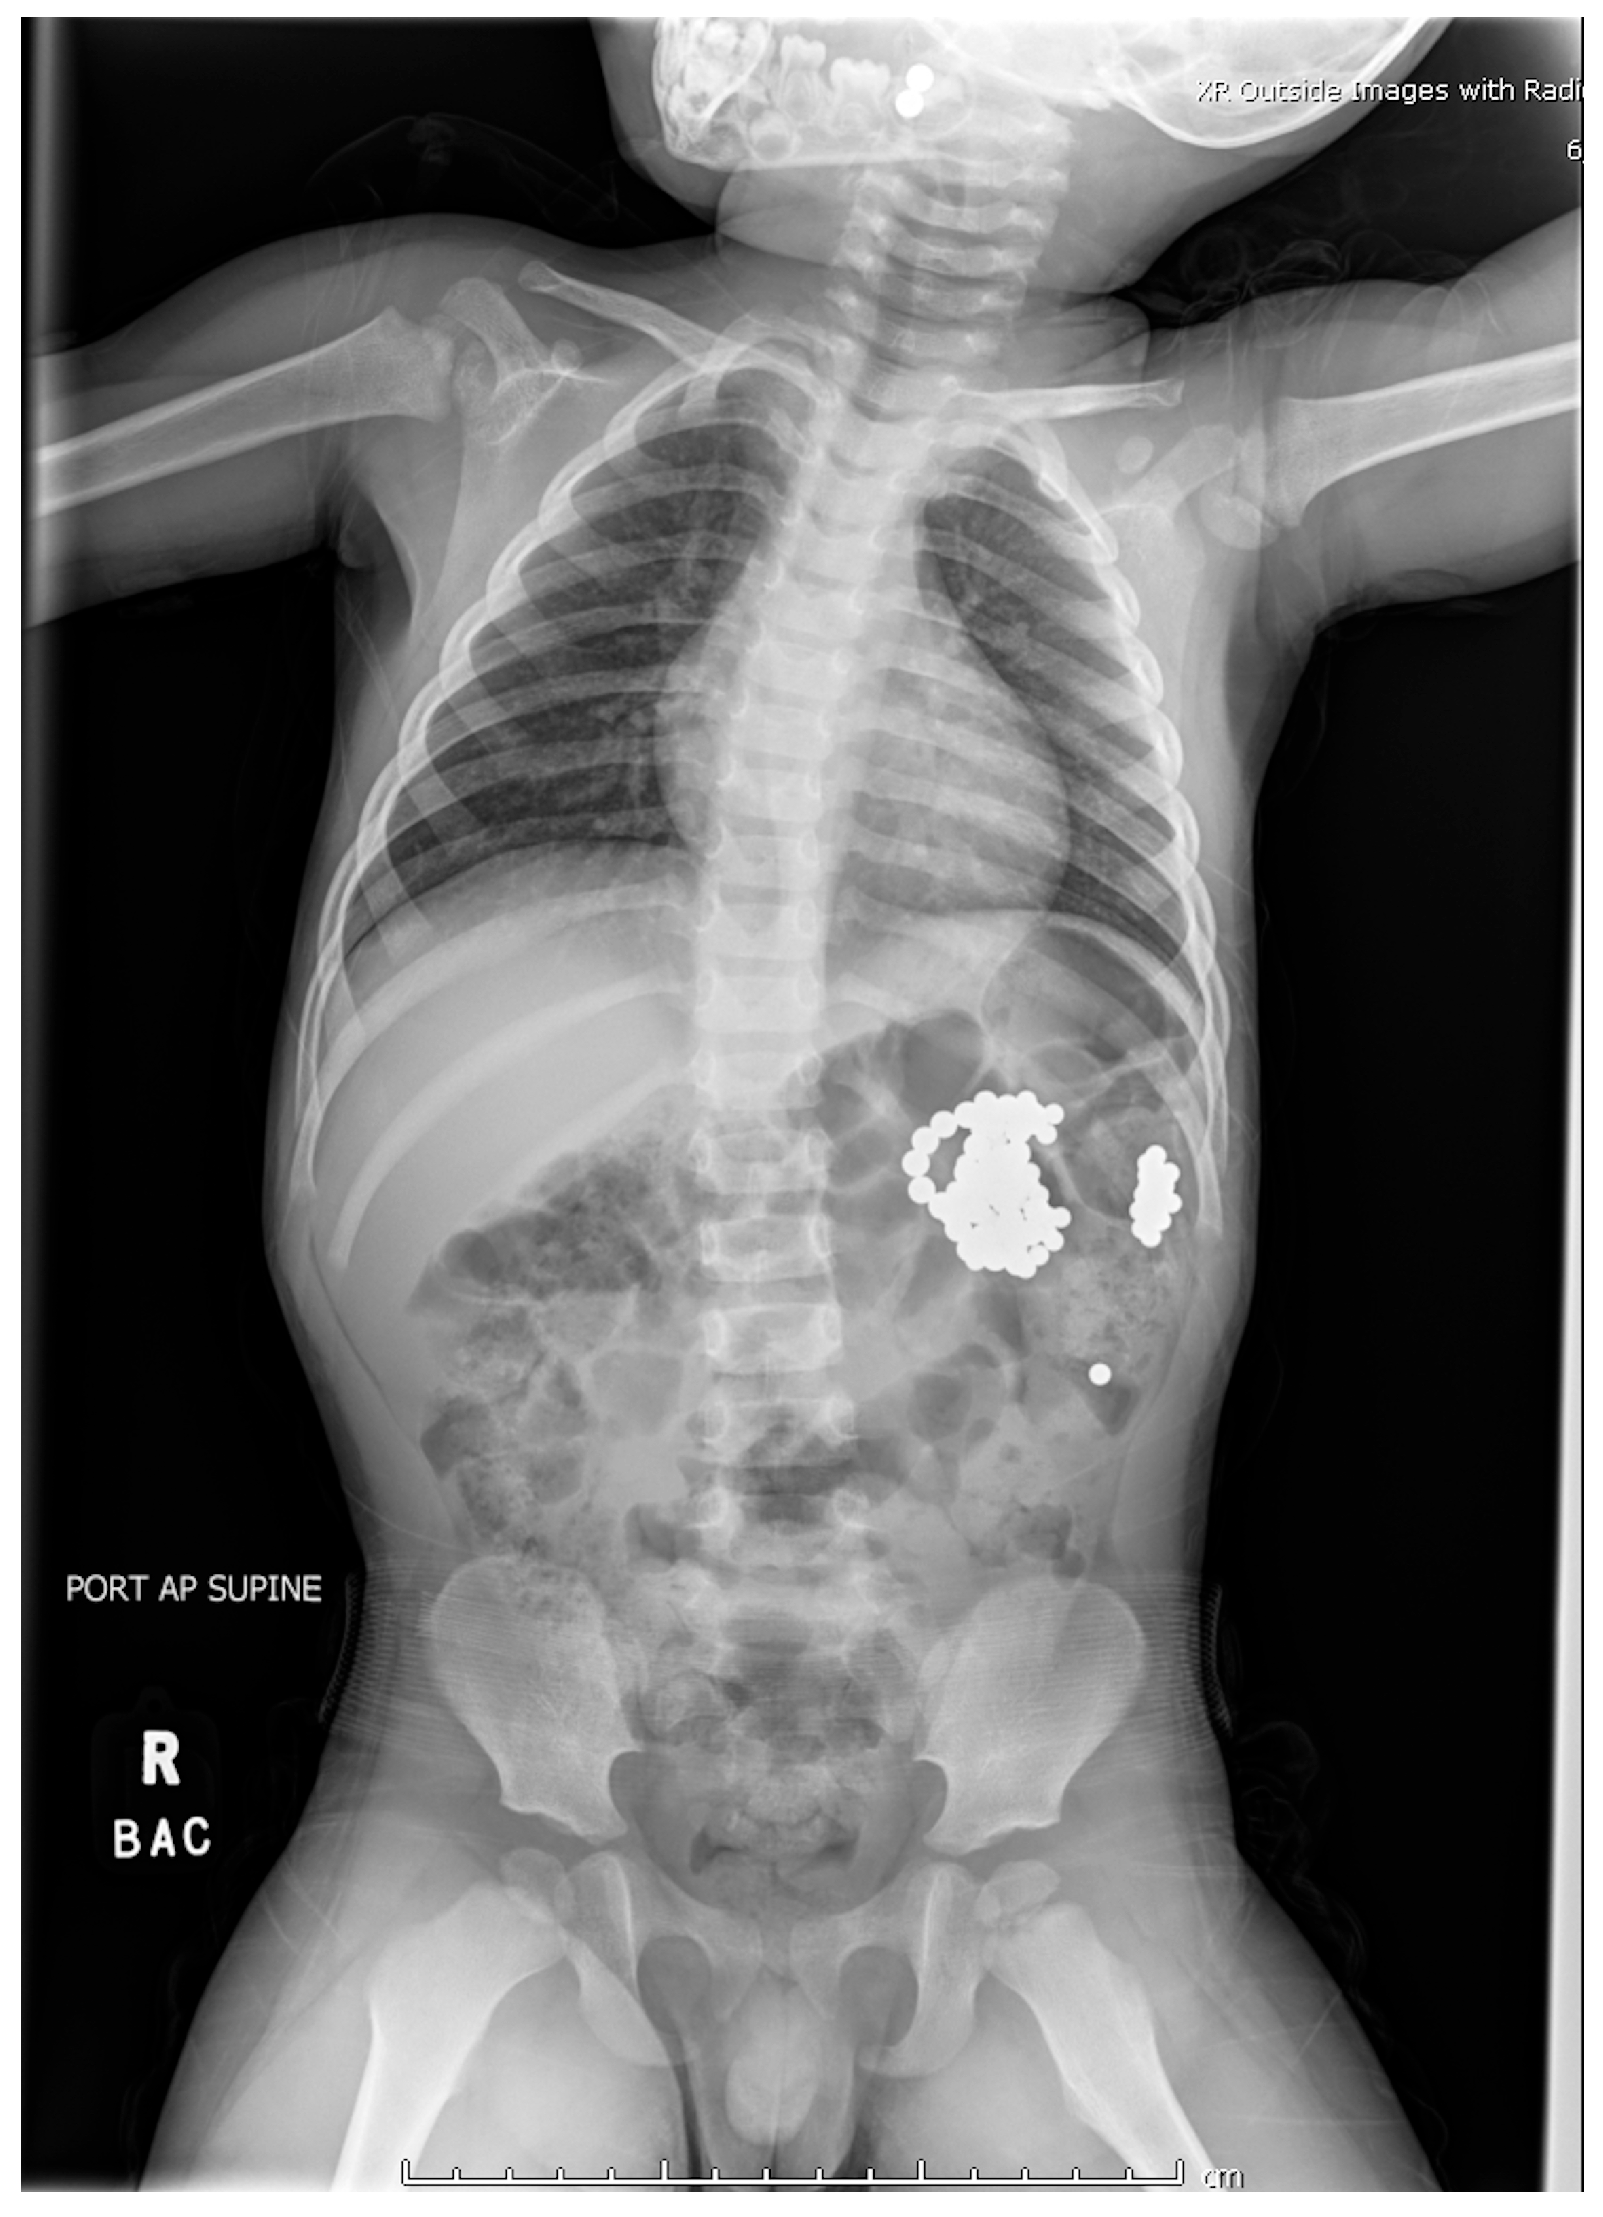

Interventions occurred across multiple anesthetic settings. Otolaryngology performed direct laryngoscopy, successfully removing two magnets adhered to the uvula with minimal trauma, consistent with findings from previous studies [4]. Gastroenterology then conducted an upper endoscopy, revealing a tightly clustered arch of 30 bb-sized magnets compressing the gastric incisura (Figure 2). Using a Roth net, they removed the magnets in two passes with no complications other than minor erosions on the gastric mucosa. Post-procedural imaging revealed residual magnets in the proximal jejunum (Figure 3).

Figure 2. A cluster of 30 bb-sized magnets was retrieved using a roth net in two passes. Superficial bb-sized erosions were noted on the proximal incisura.